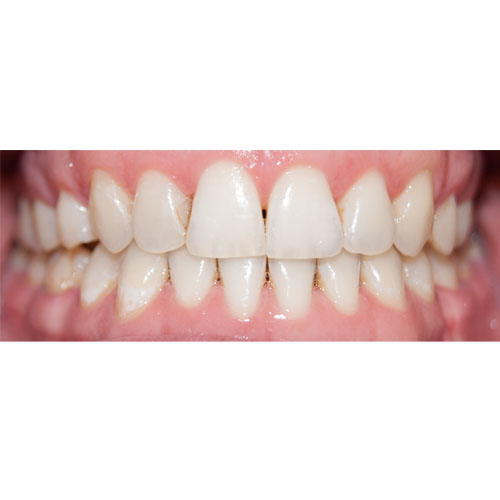

Nasze rezultaty